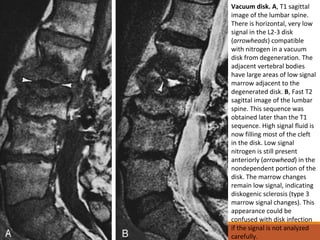

Normal e Anormal

Vácuo Discal e nos Corpos Vertebrais:

◦A degeneração do disco pode levar a dessecação do mesmo

com formação de fissuras ou fendas no material nuclear,

que pode encher-se de nitrogênio.

◦Quando este achado está presente, é essencial excluir a

possibilidade de infecção ou tumor superposto envolvendo

o disco.

◦A RM mostra o vácuo discal como espaço vazio orientado

horizontalmente com sinal linear em todas as seqüências de

pulso.

Vacuum disk. A, T1 sagittal

image of the lumbar spine.

There is horizontal, very low

signal in the L2-3 disk

(arrowheads) compatible

with nitrogen in a vacuum

disk from degeneration. The

adjacent vertebral bodies

have large areas of low signal

marrow adjacent to the

degenerated disk. B, Fast T2

sagittal image of the lumbar

spine. This sequence was

obtained later than the T1

sequence. High signal fluid is

now filling most of the cleft

in the disk. Low signal

nitrogen is still present

anteriorly (arrowhead) in the

nondependent portion of the

disk. The marrow changes

remain low signal, indicating

diskogenic sclerosis (type 3

marrow signal changes). This

appearance could be

confused with disk infection

if the signal is not analyzed

carefully.